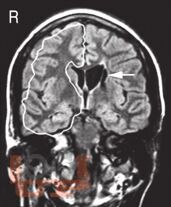

Чарльз Ньокиктьен известен как один из ведущих специалистов и основоположников нового научного направления - детской поведенческой неврологии - той области неврологии, которая изучает связь между проблемами в поведении и обучении и их неврологической основой. Впервые предлагаемый российскому читателю двухтомник обобщает современные данные неврологии и других нейронаук о развитии и отклонениях в развитии ребенка, а также неврологические и нейропсихологические методы их оценки.

Во II томе рассматриваются развитие памяти и внимания у детей и их расстройства, включая гиперактивное расстройство с дефицитом внимания, нарушения развития речи (дисфазия) и школьных навыков (дислексия, дисграфия, дискалькулия), аутистические расстройства, особые синдромы (поведенческие фенотипы), нейропсихиатрические нарушения, отставание и регресс в психомоторном развитии.